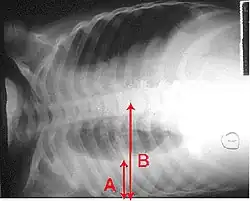

Radiografia de tórax com derrame pleural. A seta A mostra a camada de fluido na cavidade pleural direita. A seta B mostra o comprimento normal do pulmão na cavidade.

Derrame pleural é a acumulação excessiva de fluido entre as membranas que envolvem o pulmão (cavidade pleural). Uma quantidade excessiva deste fluido pode descompensar a ventilação por limitar a expansão dos pulmões (atelectasia).